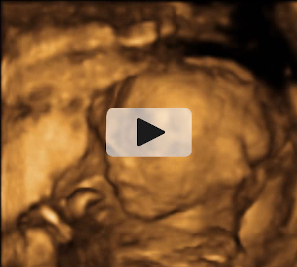

Ecografía semana 20: Cara de perfil y mano del bebé

En la semana 20 de embarazo el bebé aún se mueve libremente dentro del útero materno. Como este feto con la cara de perfil, que se apoya en la pared uterina ayudándose del puño y la nariz. Podemos ver perfectamente la mano cerrada y los dedos, así como los rasgos del perfil y el cráneo.

Cara fetal de perfil y mano frente a la pared del útero